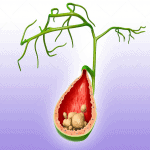

Sỏi túi mật (Gallbladder Stone) là vật thể hữu hình do sự lắng đọng và kết tinh các chất dự trữ trong túi mật với 2 thành phần chính là Cholesterol và Bilirubin. Nguyên nhân:

+ Tăng Cholesteron máu: rối loạn chuyển hóa, tăng mỡ máu, tăng đường huyết, gan nhiễm mỡ =>hình thành sỏi Cholesterol

+ Tăng sản xuất Bilirubin: viêm gan, bệnh tan máu, bệnh viêm gan tự miễn => hình thành sỏi sắc tố.